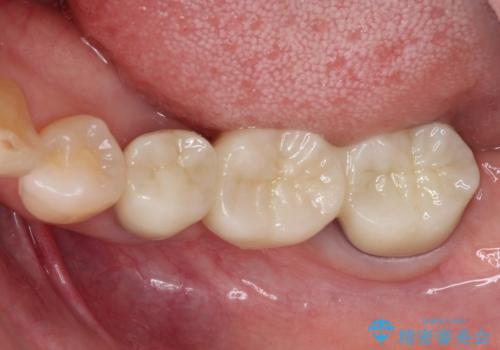

インプラントあるいはブリッジによる補綴治療が考えられましたが、前後の歯が大きな銀歯であったため、オールセラミックブリッジにより3本の歯を審美的に仕上げることとしました。

奥歯の治療をしている間に前歯の治療をどのように勧めるのか検討していただき、最終的には4歯を一度に治療し、審美的に仕上げることとしました。